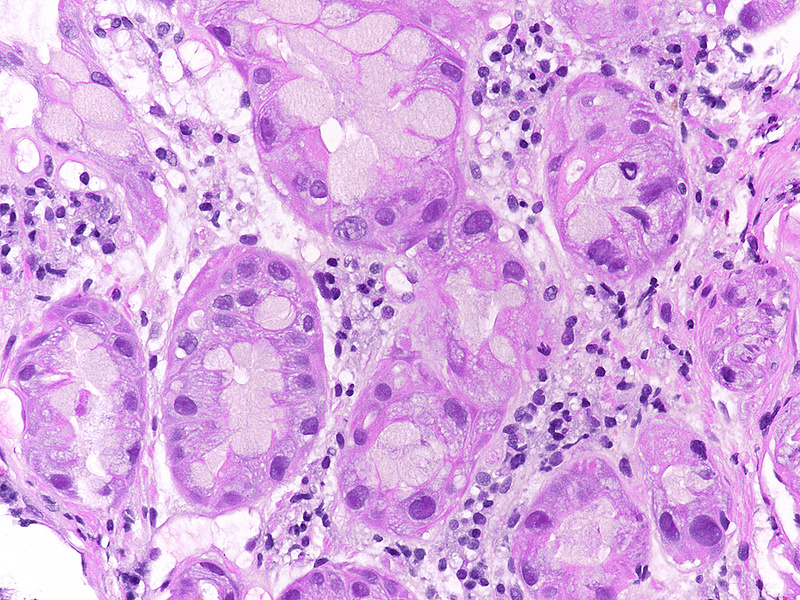

A 41-year-old female with ocular malignant melanoma, metastatic to both lobes of the liver, presented with nausea, vomiting and epigastric pain. Upon endoscopy, a large ulcerated lesion, extending from the corpus to the duodenal bulb, was detected (Panel A). Upon histology, ballooning cells with mild to moderate nuclear atypia were observed within the surface and foveolar epithelium (Panel B-C). Marked nuclear pleomorphism, hyperchromasia and loss of polarity, along with increased cytoplasmic eosinophilia were present within the deep gastric glands (Panel D). Mitotic figures were not seen, and  the  Ki-67 labelling index was low (Panel E). p53 overexpression was noted in the atypical cells, however with  heterogeneous staining, thereby indicating an activated wild-type pattern (Panel F).

The presented case demonstrates severe atypia of the gastric epithelium, which exceeds what is typically seen in ischaemic injury and may lead to the erroneous diagnosis of dysplasia and/or malignancy. Drug toxicity explains these findings. Specifically, fotemustine causes interstrand crosslinking of DNA, which prevents DNA replication, and ultimately leads to apoptosis in a p53 dependent manner. Interestingly, Ki-67 labeling was low in our case. This may be attributable to the fact that the highest levels of nuclear Ki-67 staining are reached during the M phase of the cell cycle, which the epithelial cells failed to enter due to the drug effect (Varelas et al. 2022).